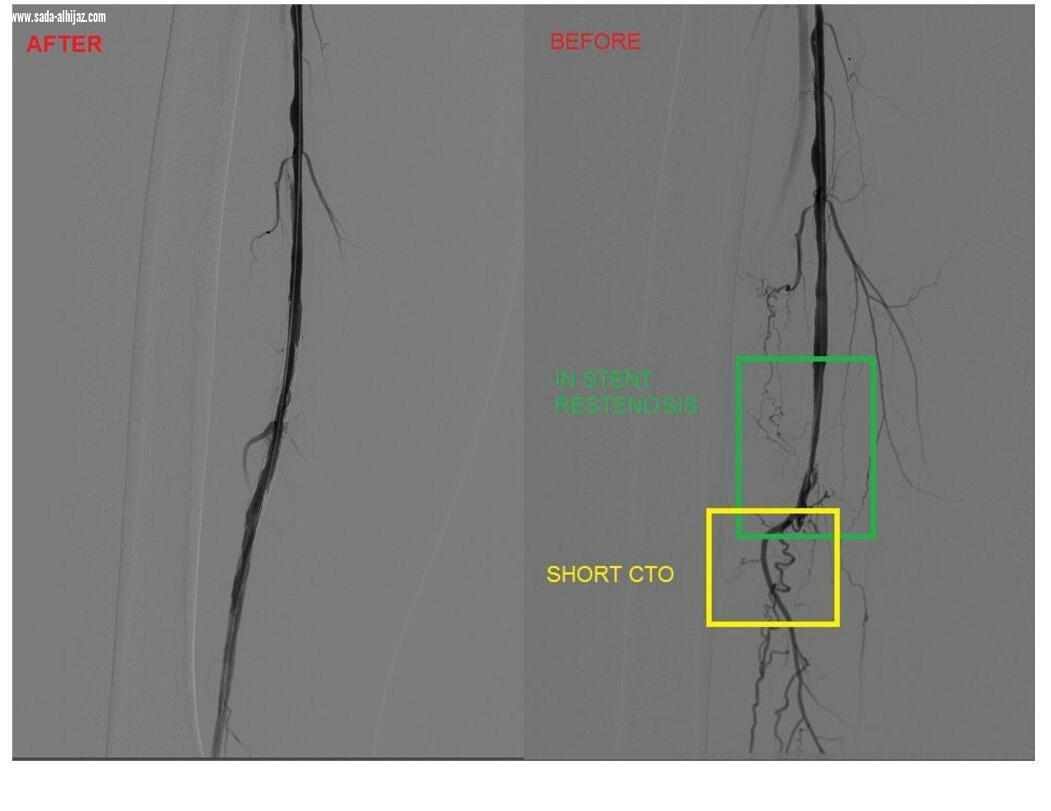

و في التفاصيل باشر الفريق الطبي الإسعافي حالة المواطن بقسم الطوارئ و الكوارث بالمجمع الطبي و هو يعاني من آلام حادة في الساق الأيمن و إرتفاع السكر في الدم بالكشف المبدئي الذي من خلاله تم إجراء كامل الفحوصات الطبية الإشعاعية و المخبرية اللازمة و التي أظهرت نتائجها وجود تضيق في القدم اليمنى و إنسداد كامل في شريان الفخذ السطحي ، و لخطورة ذلك على صحة المريض من حدوث أي مضاعفات لا سمح الله تم تنويم الحالة بشكل عاجل نظراً لوجود مراجعات علاجية قائمة في العيادات الخارجية التابعة لمركز القلب التخصصي بالمجمع الطبي إضافة إلى وجود تاريخ مرضي سابق للحالة مزمن مع مرض السكري .

و على الفور تم التنسيق الطبي مع فريق وحدة الأشعة التداخلية بالمجمع لدراسة الحالة و معالجتها عبر خدمة نوعية حديثة لعلاج إنسداد الشرايين الطرفية بإستخدام جهاز إزالة الجلطات ، و تكون الحالة بذلك أول حالة مرضية تُقدم لها الخدمة العلاجية بمجمع الملك عبدالله عبر هذا الجهاز بإختلاف الإجراء الروتيني المعتاد عليه بوضع دعامات لتوسع الشرايين المتضيقة و من غير تدخل جراحي ، عن طريق فتحة صغيرة في الشريان الفخذي الذي أثبت فعاليته في إزاله جلطات الشرايين المتكلسه و جلطات الأوردة الحادة و المزمنة للحالة ، حيث يُستخدم الجهاز لعلاج الحالات المرضية الذين يعانون من نقص في تروية القدم أو من جلطات الأوردة الطرفية .